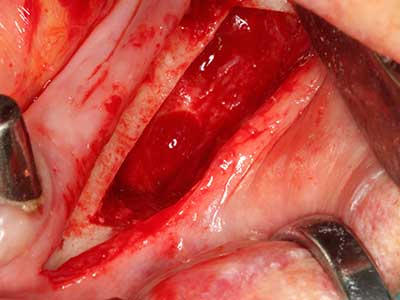

Fig. 6: After preparation of a mucoperiosteal flap, access to the maxillary sinus is prepared piezoelectrically.

Fig. 7: The initial preparation of the sinus mucous membrane can also be performed ultrasonically.